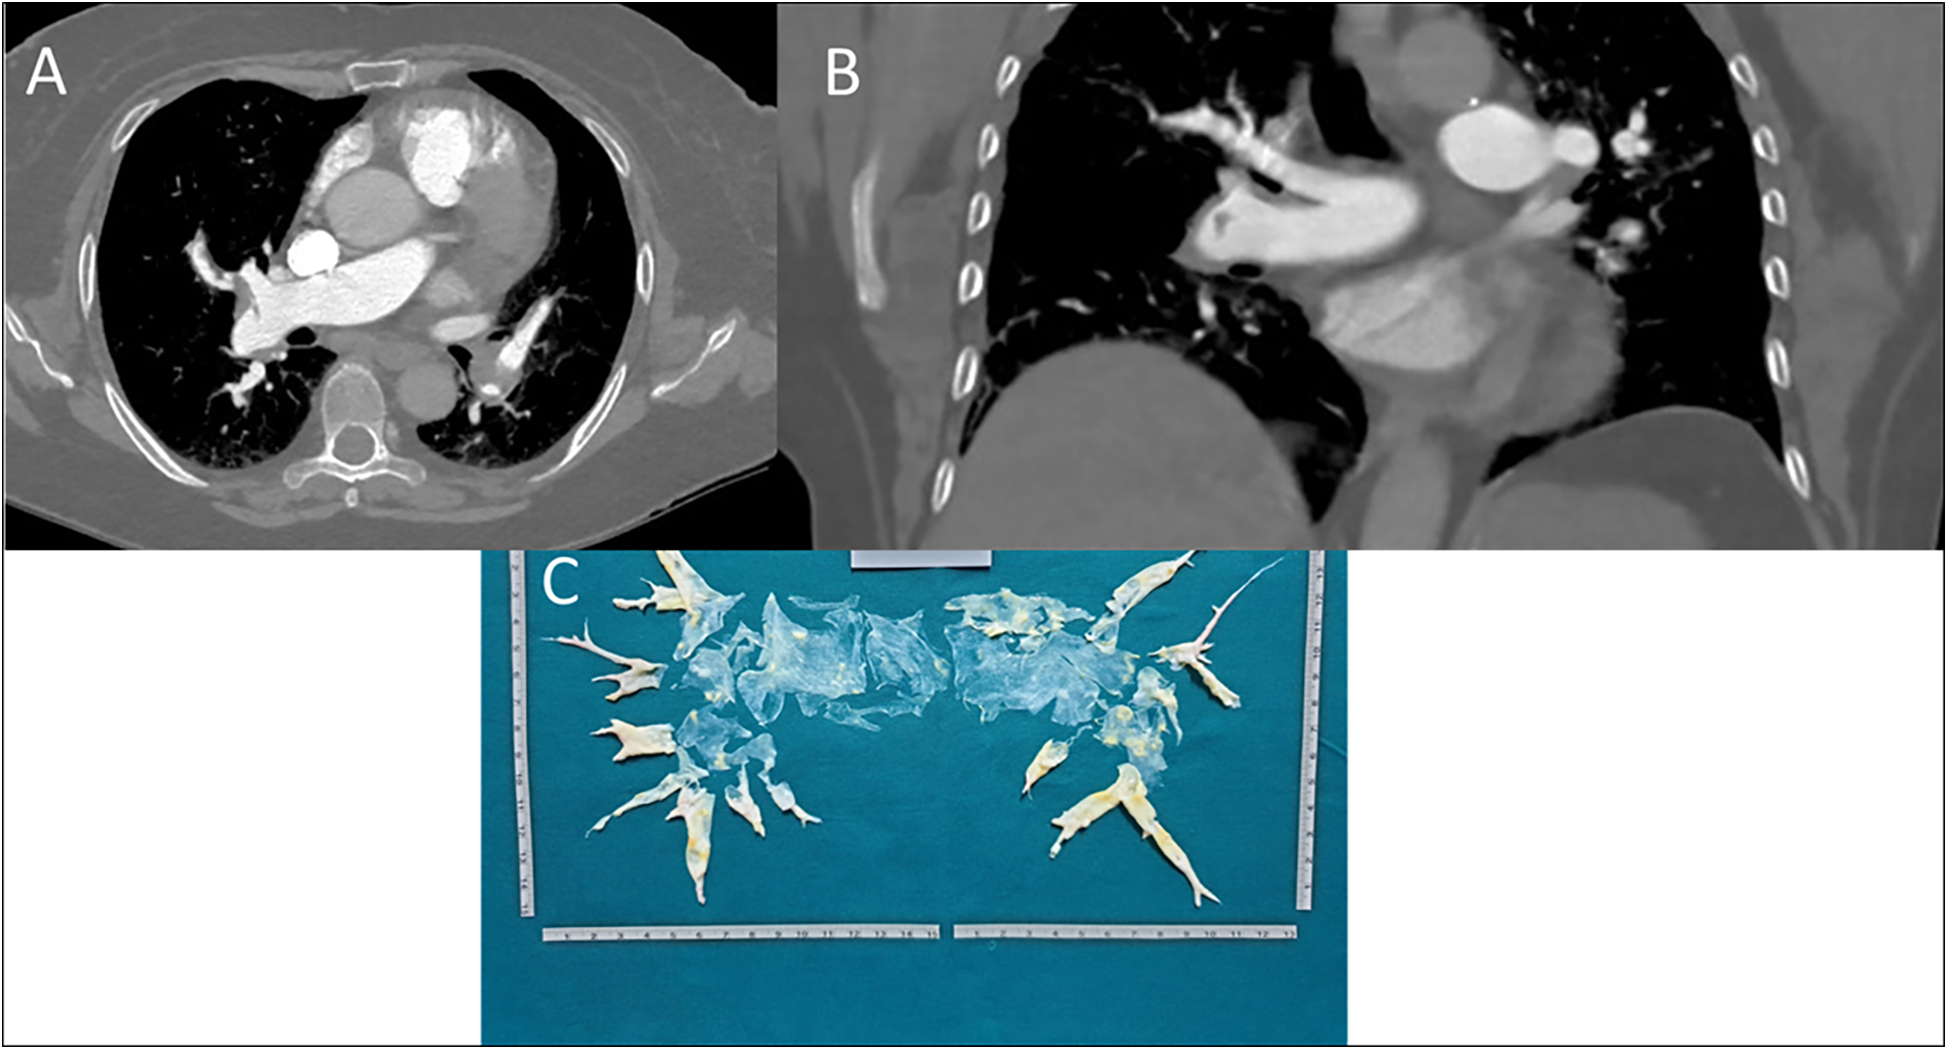

Figure 2

(A) axial scansion of chest CT with contrast. A filling defect of a thrombo-embolic nature in the right pulmonary artery, between the middle and lower lobe tributary branches, can be observed. The arrow also shows small thrombi in the left pulmonary artery branches. (B) Coronal scansion of chest CT with contrast. A filling defect of a thrombo-embolic nature in the branch of the right pulmonary artery tributary to the lower lobe can be observed. (C) Postoperatively surgical finding of pulmonary thromboendarterectomy.

In February 2021, due to worsening dyspnea over a few weeks, including symptoms at rest (Class IV of WHO functional classification), the patient was admitted to a hospital. Blood gas analysis revealed type 1 respiratory failure requiring oxygen therapy. The complete blood count, including a platelet count of 248 k/μl, and the D-dimer level (688 ng/ml) were within normal limits. However, the pro-brain natriuretic peptide (pro-BNP) was mildly elevated at 881 pg/ml. Echocardiographic findings suggested a high probability of pulmonary hypertension, and axial computed tomography revealed partial filling defects in the segmental and sub-segmental branches of the pulmonary arteries, consistent with CTEPH (Figures 2A,B). A ventilation/perfusion (V/Q) scan and right heart catheterization (RHC) were performed, showing bilateral ventilation-perfusion mismatch and pre-capillary pulmonary hypertension with a severe reduction of cardiac index (CI) [mean pulmonary arterial pressure (mPAP) 41 mmHg, Pulmonary Artery Wedge Pressure (PAWP) 12 mmHg, pulmonary vascular resistance (PVR) 8 WU, CI 1.7 L/min/m2]. Histological examination of the thrombus confirmed that it was composed of platelets, collagen, and fibrin, having undergone reorganization over time. Therapeutic measures included discontinuation of Eltrombopag, increased corticosteroid dosage, and replacement of Rivaroxaban with Fondaparinux 10 mg daily (patient weight over 100 Kg). The patient was referred for PTE at the Cardiac Surgery Center (Figure 2C). In the immediate pre-operative period, intravenous immunoglobulins were administered due to the significant reduction of platelets. Given the thrombophilic diathesis, a caval filter was placed during the procedure, and anticoagulation therapy with vitamin K antagonists was initiated. At the end of the intervention, an immediate and pronounced decrease in mPAP values was observed. This finding was confirmed by pre-discharge right heart catheterization (RHC), which showed a 47% reduction in mPAP, a 71% reduction in PVR and a 38% increase in cardiac output. Finally, the patient no longer required daytime oxygen therapy.